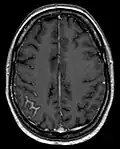

| Meningeal carcinomatosis: tumor cell clusters in the subarachnoid space in a brain biopsy | |

Meningeal carcinomatosis in a patient with breast cancer (contrast-enhanced axial T1-weighted MRI)